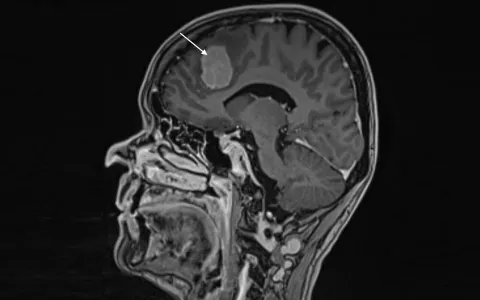

Aivoja ympäröivistä aivokalvoista lähtöisin oleva meningeooma on yleisin hyvänlaatuisista aivokasvaimista. Meningeoomia hoidetaan pääasiallisesti neurokirurgisilla leikkauksilla. Koska leikkaushoidon riskit lisääntyvät iän ja muiden sairauksien myötä, yli 80-vuotiaita aivokasvainpotilaita ei suuressa osassa maailmaa leikata.

Aikaisemman tutkimusnäytön puutteellisuuden vuoksi Helsingin yliopisto ja HUS ovat tutkimuksessaan selvittäneet leikkausten tuloksia. Tutkimus koostui kaikista HUS neurokirurgian klinikassa vuodesta 2010 lähtien leikatuista 80-vuotiaista tai vanhemmista meningeoomapotilaista. Potilaita oli yhteensä 83. Tutkimuksen tulokset on julkaistu vastikään Scientific Reports -tiedelehdessä.